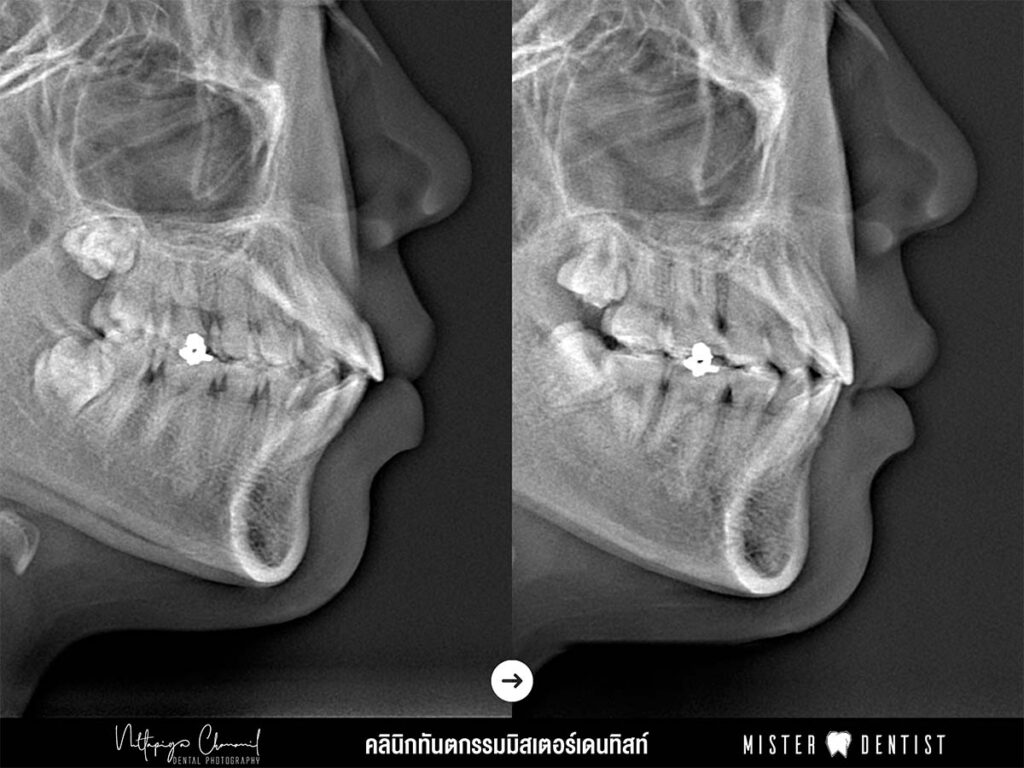

รูปที่ 8 เปรียบเทียบภาพถ่ายเอกซเรย์

จากรูปที่ 8

(รูปซ้าย) ก่อนจัดฟัน จะพบว่าปากมีความอูมชัดเจน และฟันดูยื่นออกมาชัดเจน

(รูปขวา) หลังจัดฟัน ปากอูมลดลง และฟันเรียงตัวสวยไม่งุ้ม